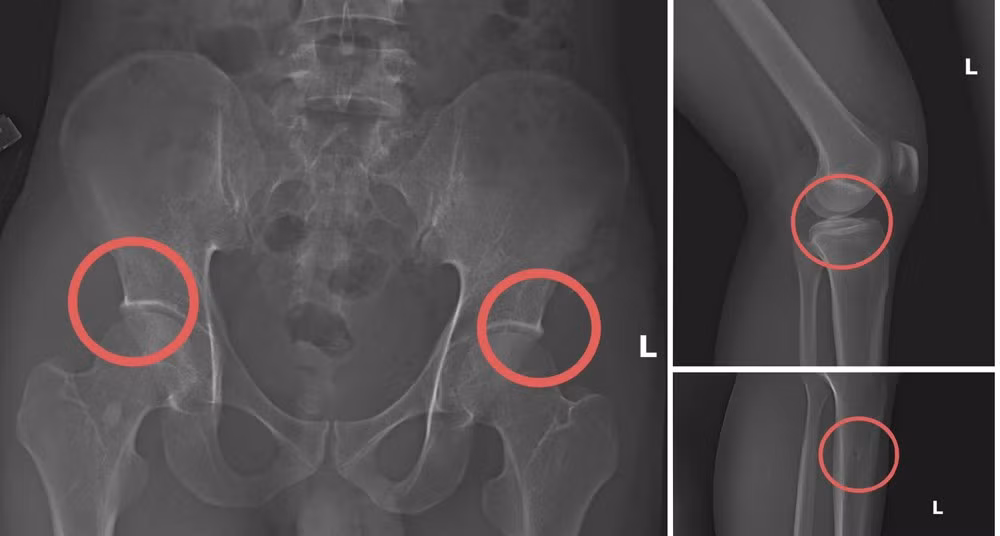

Bản phim chụp XQ một số tổn thương xương do đối tượng tạo ra nhằm trục lợi tiền bảo hiểm nhân thọ.

Lợi dụng thời gian dài công tác trong ngành y và am hiểu sâu cấu tạo xương-khớp, cũng như cơ chế chi trả bảo hiểm đối với các thương tích gãy xương giá trị cao, Châu đã dựng lên một quy trình trục lợi bài bản, từ việc vận động mua bảo hiểm, tổ chức gây thương tích, đến hợp thức hóa hồ sơ bệnh án để chiếm đoạt tiền của các công ty bảo hiểm.

Đáng chú ý, Châu trực tiếp thực hiện hành vi tiêm thuốc mê rồi dùng kim tiêm, búa để tác động vào xương người mua bảo hiểm, tạo nên các vết vỡ xương tương tự tai nạn thật. Khi thương tích đã tạo xong, Châu tiếp tục hướng dẫn các đối tượng dựng hiện trường giả như điện giật ngã, trượt chân ngã suối nhằm hợp thức hóa bệnh án và hoàn thiện hồ sơ yêu cầu chi trả.